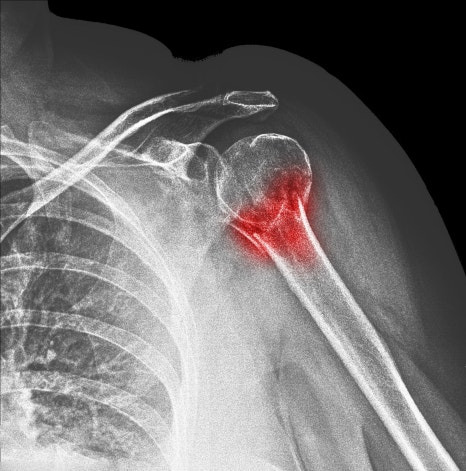

석회성건염은 어깨 힘줄에 석회가 침착되는 질환을 말합니다. 여기서 말하는 석회는 쉽게 말해 칼슘 성분 덩어리인데, 이 물질이 힘줄 내부에 쌓이게 되면 주변 조직에 염증 반응이 나타나면서 통증이 발생할 수 있습니다. 이 질환은 다음과 같은 과정을 거쳐 나타나는 것으로 알려져 있습니다.

1. 힘줄 조직의 미세 손상

2. 칼슘 침착 형성

3. 석회 주변 염증 반응

4. 통증 발생

특히 석회가 흡수되는 시기에는 통증이 갑자기 심해지는 경우도 있습니다. 그래서 많은 분들이 어느 날 갑자기 어깨가 너무 아프다고 이야기하기도 합니다. 이러한 특징 때문에 양쪽어깨통증이 갑자기 시작되는 경우에도 석회성건염이 원인이 되는 경우가 있습니다.